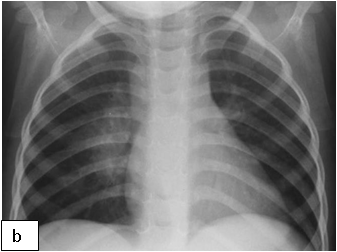

Chest x-ray is not usually diagnostic but may show bilateral diffuse parenchymal infiltrates with a “ground-glass” or reticulogranular appearance, but can be normal or have only mild parenchymal infiltrates. The earliest infiltrates are perihilar, progressing peripherally before reaching the apical portions of the lung.

Chest X-ray (CXR): TB enlarged perihilar lymph nodes are better visualised on a lateral CXR than a PA view, therefore, it is important to obtain both PA and lateral films when evaluating a child with suspected TB.

Presentation: The signs and symptoms of CMV disease often overlap with other infectious processes, therefore, the diagnosis of CMV disease in HIV-infected children should take into consideration clinical presentation and radiological finding along with laboratory testing. CMV pneumonia presents with fever, dyspnoea and hypoxemia. A chest radiograph shows diffuse pulmonary infiltrates (ground glass appearance) as seen in other viral pneumonias and PCP. The isolation of CMV from isolates including BAL does not prove that the child has CMV pneumonia. Co-infection with both PCP and CMV is common.